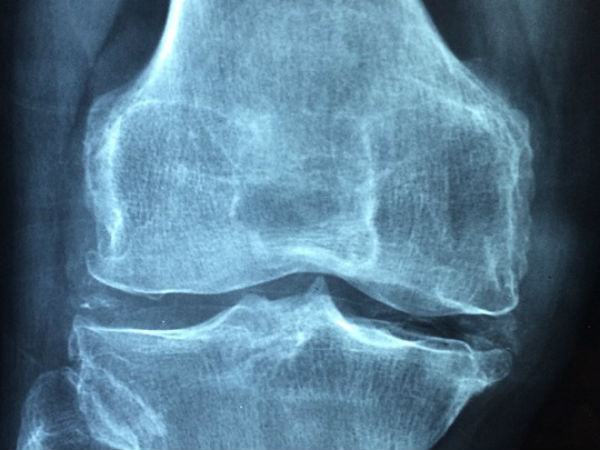

முழங்காலில் உள்ள மூட்டு, இரண்டு பக்க எலும்புகளுக்கு இடையே பந்துபோல உருண்டுகொண்டு இருக்கிறது. பல்வேறு காரணங்களால் இரு எலும்புகளுக்கும் இடையே உள்ள சவ்வு சேதம் அடைவதால், மூட்டு இயங்குவதில் பாதிப்பு ஏற்படுகிறது. இது வலி, வீக்கத்தில் தொடங்கிக் கடைசியில் நடக்க முடியாத நிலையை உருவாக்கிவிடுகிறது.

தொடை எலும்பின் கீழ்ப்பகுதியும் முழங்கால் எலும்பின் மேல் பகுதியும் இணைகின்ற இடமே முழங்கால் மூட்டு இது உடல் எடையைத் தாங்குகின்ற முக்கியமான மூட்டு.

முழங்கால் மூட்டைத் தொட்டுப் பார்த்தால், நம் கைக்குத் தட்டுப்படுவது முழங்கால் மூட்டுச் சில்லு (Knee cap). முழங்கால் மூட்டுக்கு நேரடியாக பாதிப்பு ஏற்படுவதைத் தடுப்பதற்காக இயற்கை நமக்குக் கொடுத்திருக்கிற பாதுகாப்பு மூடி இது. இதற்குப் பின்னால் உள்ளதுதான் உண்மையான முழங்கால் மூட்டு.

மூட்டில் தேய்மானம் மிக அதிகமாக இருந்தால், மூட்டுவலிக்கு முழுமையான தீர்வு தருவது, ‘செயற்கை மூட்டு மாற்று சிகிச்சை' ‘மூட்டு மாற்றம்' என்றதும் முழங்கால் மூட்டு மொத்தத்தையும் அப்படியே எடுத்துவிட்டு, உலோக மூட்டை அங்கு பொருத்தி விடுவதாக அர்த்தம் செய்துகொள்ளக்கூடாது.

மூட்டில் குருத்தெலும்பு உள்ள மேல்தளத்தை மட்டுமே இதில் மாற்றுகிறார்கள். மூட்டு மாற்று அறுவை சிகிச்சை மேற்கொள்வதற்கு முன்னதாக நீங்கள் கவனிக்க வேண்டிய விஷயங்கள்.